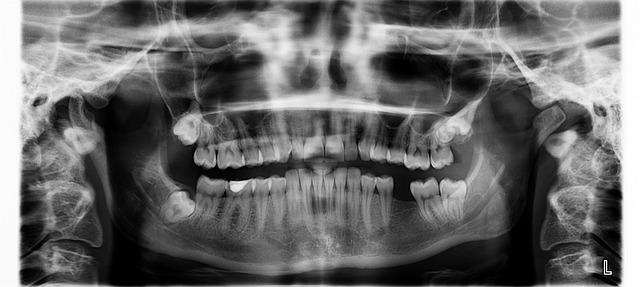

부정교합은 치아의 이상적인 교합 상태가 아닌 상태를 의미합니다. 일반적으로 상·하악 치아들이 정확하게 맞물리지 않거나 교합이 부적절한 경우를 말합니다. 부정교합은 다양한 원인에 의해 발생할 수 있으며, 개인의 구강 구조, 치아의 크기와 위치, 교합근, 턱관절 등이 관련되어 있습니다.

부정교합은 다양한 원인에 의해 발생할 수 있습니다. 가족 중에 부정교합이 나타나는 경우, 유전적인 영향이 있을 수 있습니다. 유전자가 치아와 턱의 크기, 형태, 위치 등에 영향을 주어 교합의 불균형을 일으킬 수 있습니다. 어린이의 치아와 턱은 성장과정에서 변화하며, 이로 인해 부정교합이 발생할 수 있습니다. 치아의 발육이 비대칭적이거나 턱의 크기와 치아의 크기가 맞지 않을 경우 부정교합이 발생할 수 있습니다. 혀 앞으로 튀는 습관, 입을 가만히 열어두는 습관, 손가락이나 손목을 이용한 물체를 물거나 문지르는 습관 등은 부정교합을 유발할 수 있습니다. 외상이나 사고로 인해 치아나 턱에 손상이 발생하면 교합에 이상이 생길 수 있습니다. 턱관절의 이상이나 치아의 이상적인 위치를 방해하는 구조적 문제도 부정교합의 원인이 될 수 있습니다. 그 밖에 스트레스나 불안 상태에 있는 사람들은 부정교합을 보일 수 있습니다. 이러한 경우에는 스트레스 관리와 심리적인 지원이 필요할 수 있습니다.

부정교합의 치료는 개인의 상황과 부정교합의 원인에 따라 다양하게 접근될 수 있습니다. 교정치과의사와의 상담을 통해 교정치료를 선택할 수 있습니다. 교정치료는 치아와 턱의 위치와 교합을 개선하기 위해 다양한 치과 교정기를 사용하는 것을 의미합니다. 그러나 심미적으로만 접근한 교정치료는 턱관절과 경추의 문제로 연결될 수 있으니 전신을 바로잡을 수 있도록 할 수 있는 전문 의사를 잘 찾아야 합니다. 구강 보건 전문가는 올바른 구강 관리 기술과 입안 자세를 가르쳐 줄 수 있습니다. 개인에게 맞는 칫솔, 치실 사용법과 구강 청결 유지에 대한 교육을 받는 것이 중요합니다. 부정교합이 턱 관절 문제와 관련이 있는 경우, 턱관절 치료를 통해 부정교합을 개선할 수 있습니다. 이를 위해 턱관절 재교육, 마사지, 물리치료 등의 치료 방법을 사용할 수 있습니다. 부정교합은 각 개인의 상황에 따라 다양한 원인이 있을 수 있으므로, 개인 맞춤형 치료 계획이 필요합니다. 의사와 상담하여 정확한 진단과 개인에게 적합한 치료 방법을 결정하는 것이 중요합니다. 부정교합의 치료는 전문적인 도움과 지속적인 관리가 필요할 수 있습니다.